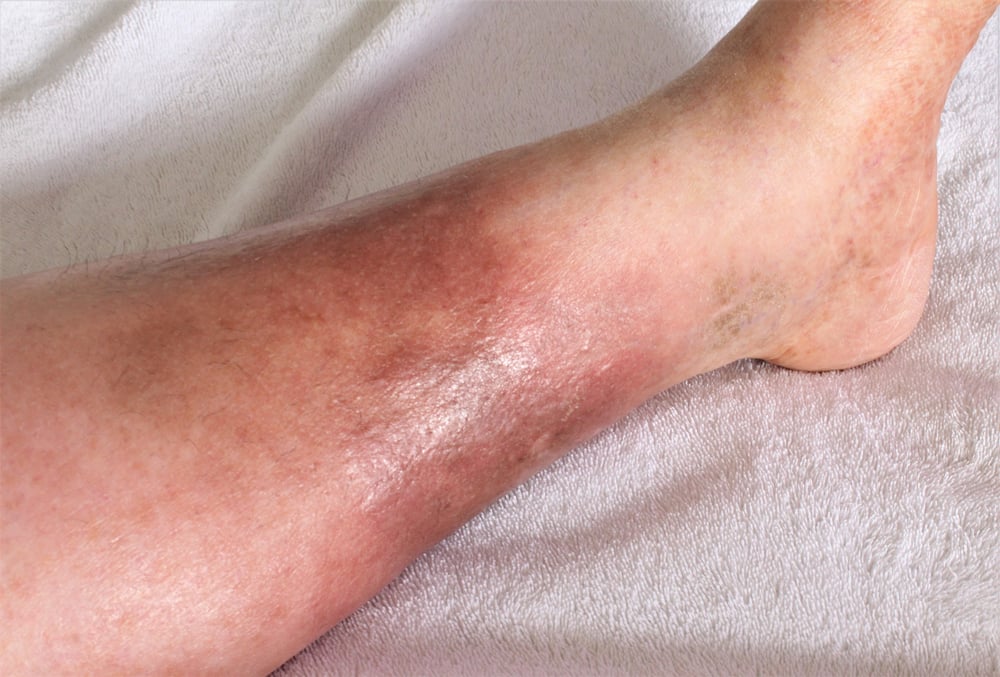

2. Visible Spider Veins Around the Ankles

Thin, web-like veins — often called spider veins — appearing around the ankles or calves could be more than just a cosmetic concern. These veins surface when there’s a hormonal imbalance, especially elevated estrogen levels, often linked to liver cirrhosis. If your liver can’t properly metabolize hormones, it can lead to vein dilation, resulting in these visible thread-like vessels.